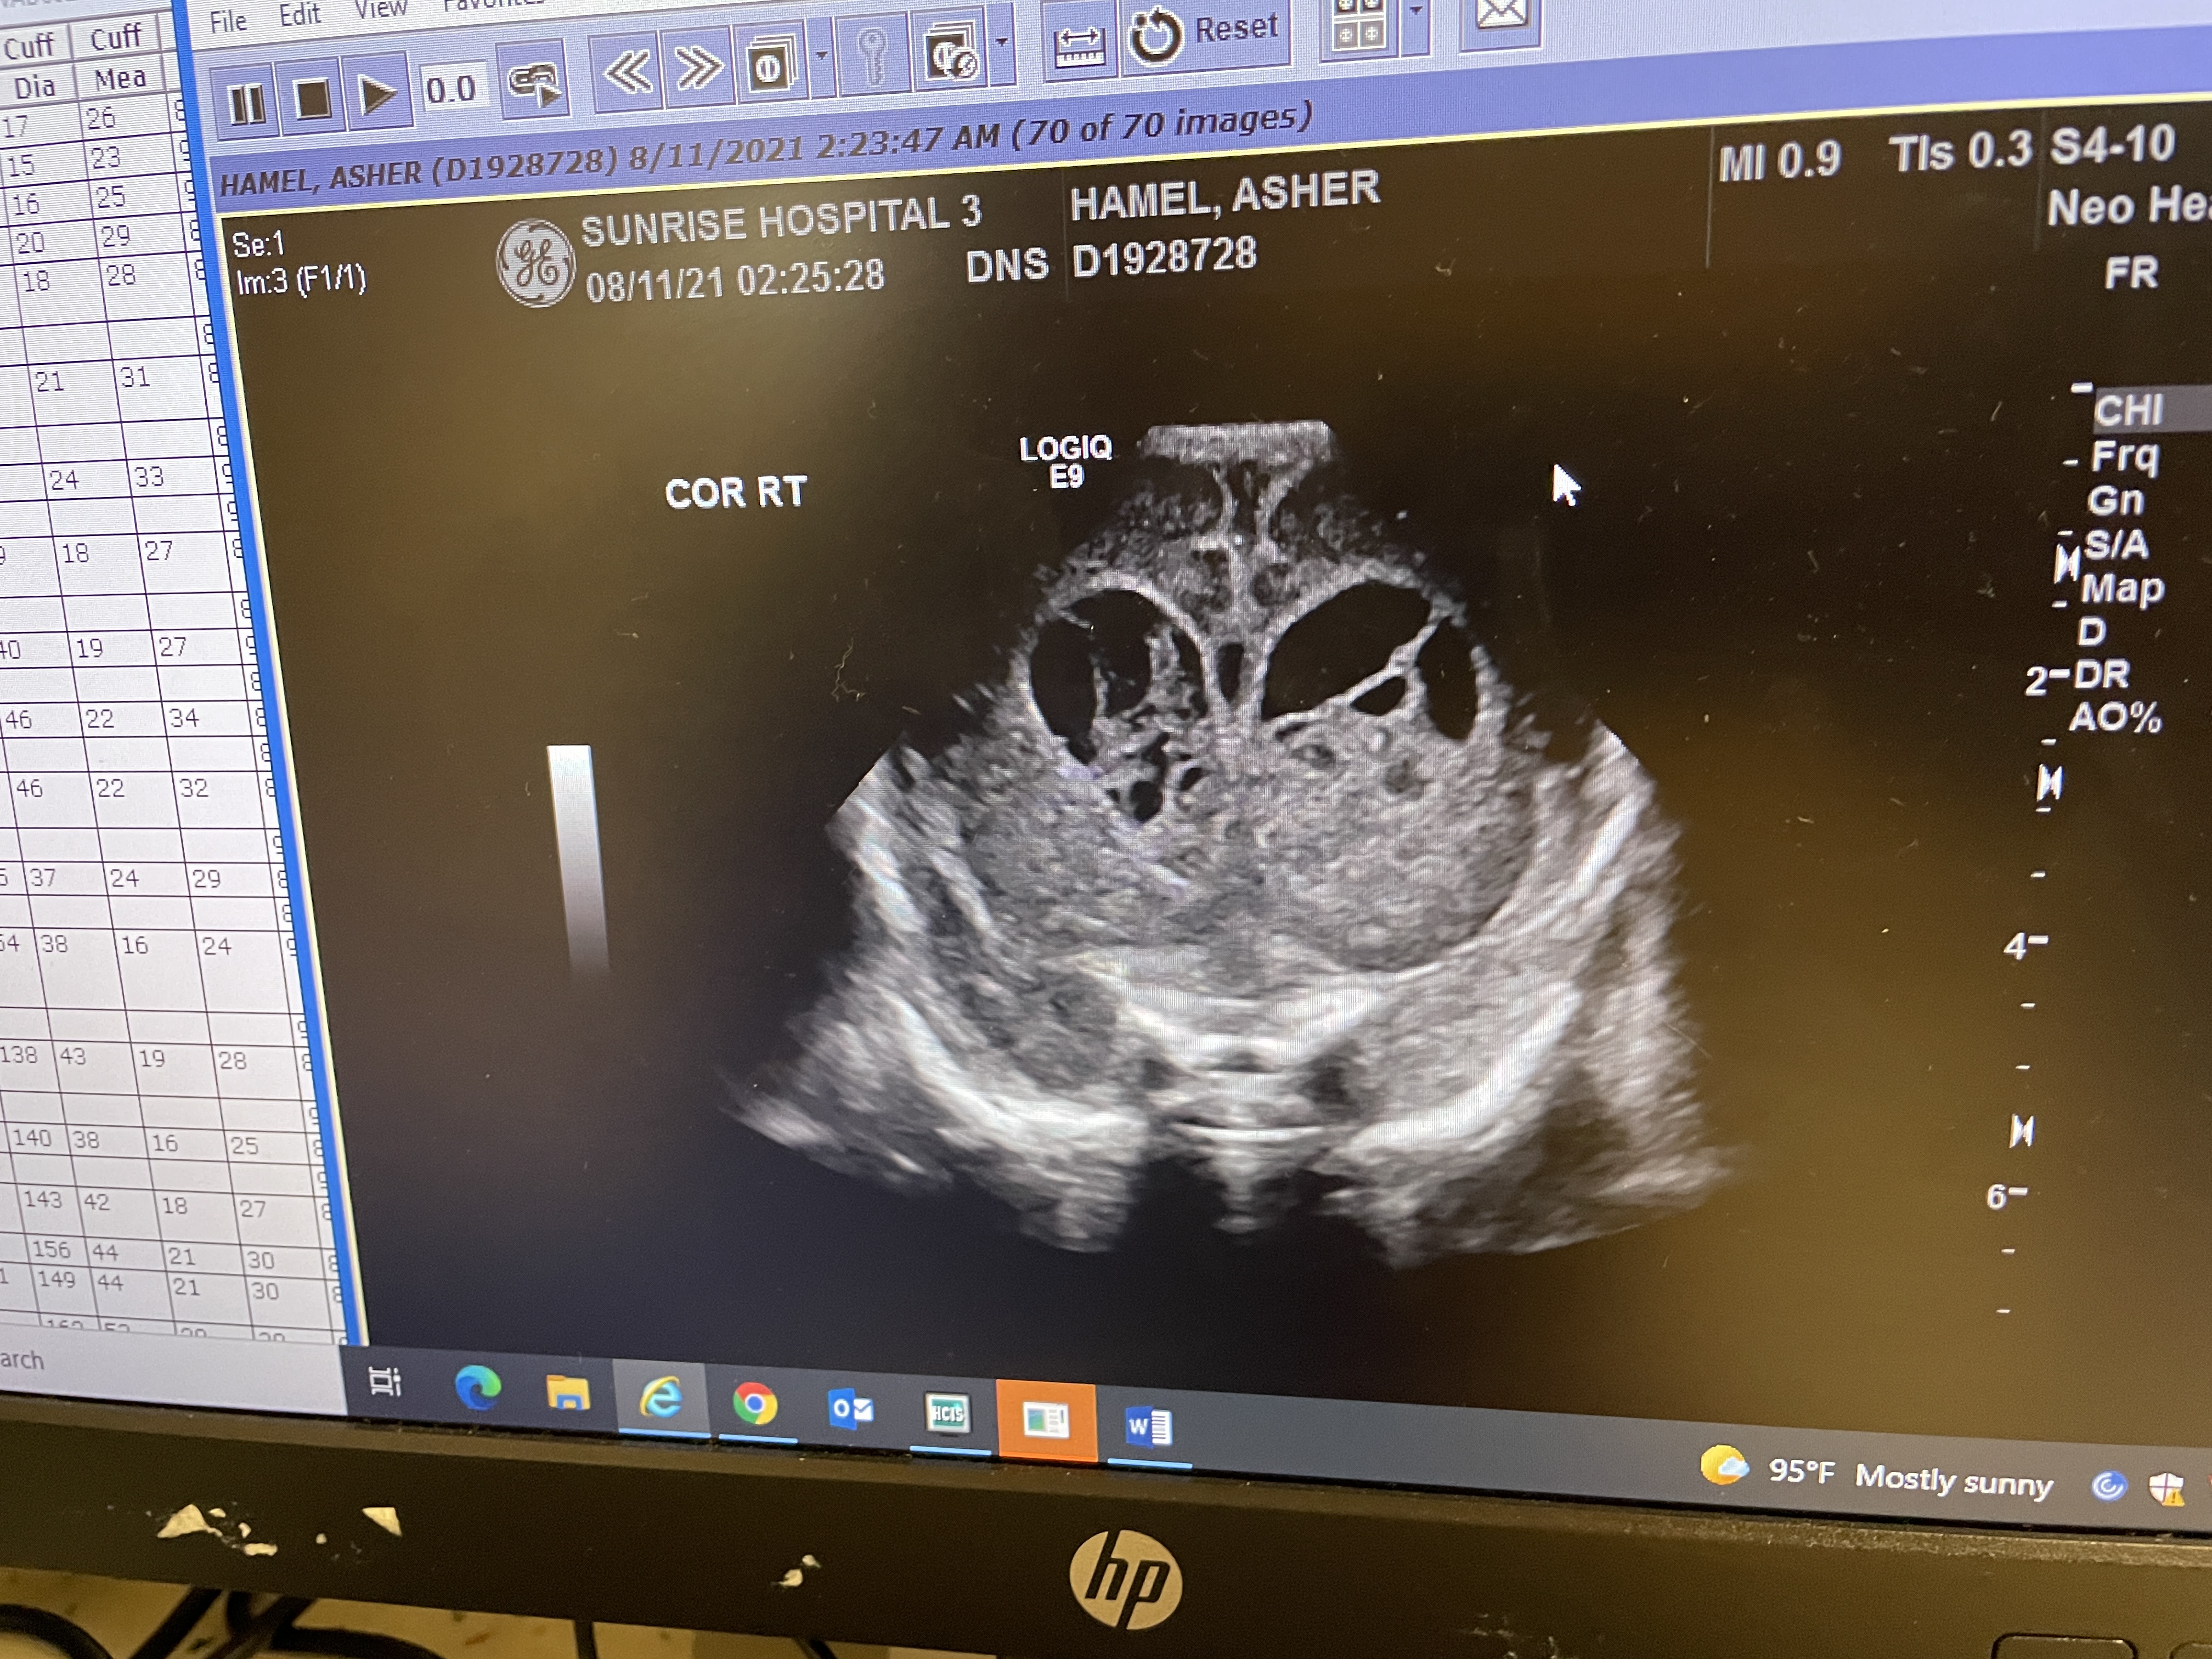

Ultrasound Images

The images show Asherās cerebral ventricles having some sort of āwebbingā inside them. His ultrasound from the week prior didnāt look like this at all. The Dr isnāt sure if itās new blood, old blood moving, or anything elseā¦

Good News: the size of his head is still within normal range. Theyāre not concerned about any abnormal growth at allā¦

The result from yesterday afternoons ultrasound are in…

They either show new bleeding (very unusual) or the way the old blood looks has changed. Dr Lipsky said it’s hard to tell and is waiting on neurosurgeon to review the images…

She did say that it looks as if there’s septation in his ventricle/s (some stringy stuff) but isn’t sure. We’ll be getting a clearer definition of septaion once we get to the hospital today. She did mention “something has definitely changed in his brain and that it could be an abscess as well.”